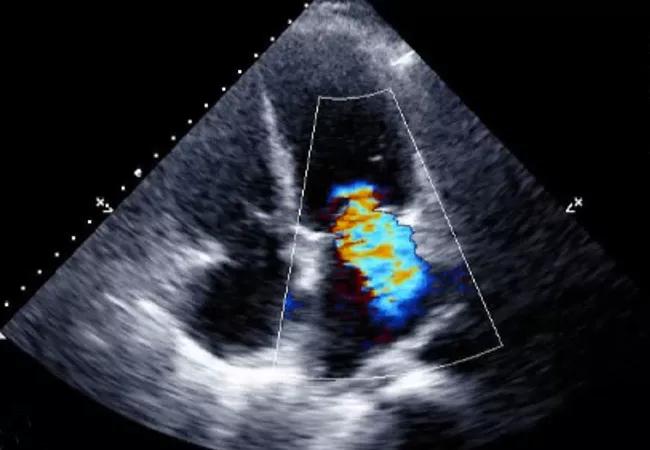

MRI assessments of myocardial scarring (top), mitral valve geometry (middle) and mitral regurgitation (bottom).